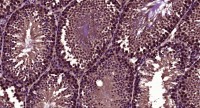

WB analysis of various samples using GTX12386 CD134 antibody.

Lane 1 : mouse brain tissue lysate

Lane 2 : mouse spleen tissue lysate

Lane 3 : mouse liver tissue lysate